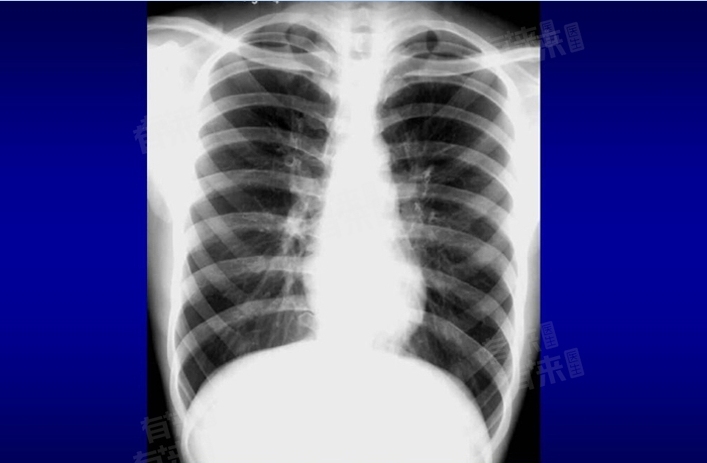

肺索条状影,作为一种在肺部影像学检查中常见的描述,通常是指肺部出现的纤维条索状密度增高影。针对这一问题是否需要治疗,需要根据具体情况而定。

- 肺索条状影往往是肺部疾病治愈后留下的陈旧性病灶,如肺炎、肺结核等炎症性疾病在肺部形成的瘢痕组织。这些索条状影通常不需要特殊治疗,因为它们本身代表了一种稳定状态,既不会对患者产生明显的临床症状,也不会对肺功能造成显著影响。在这种情况下,医生通常会建议患者定期复查,以监测其变化情况,但无需采取积极的治疗措施。